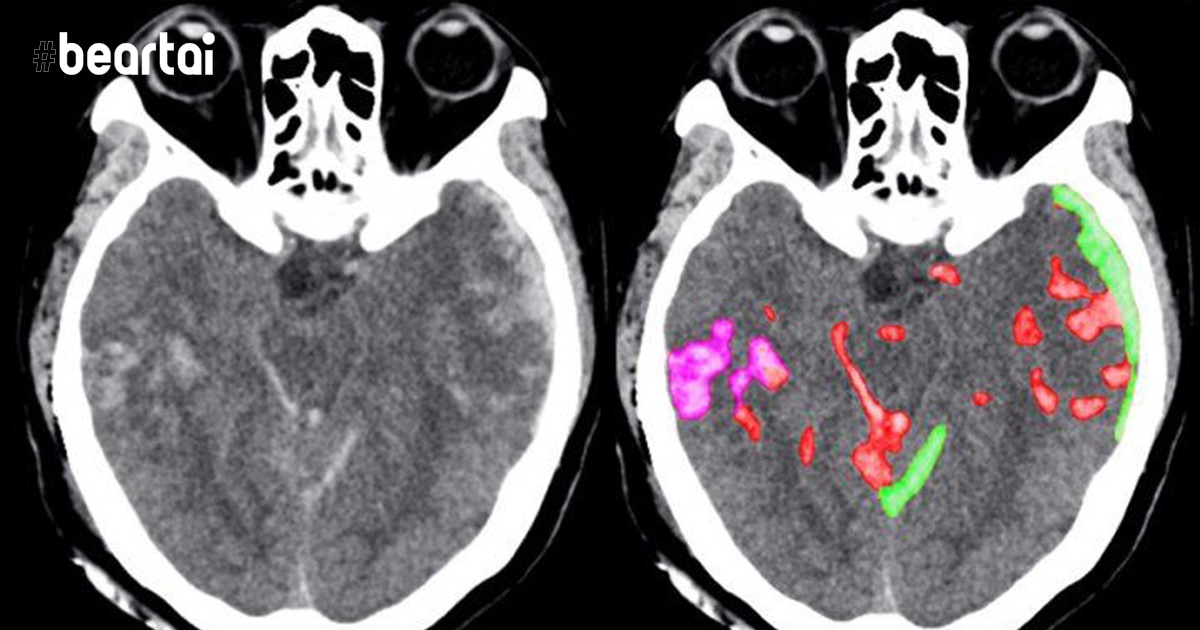

นักวิจัยจาก UC Berkeley และ UCSF ได้ออกแบบระบบที่สามารถตรวจหาอาการเลือดออกในสมองได้แม่นยำไม่แพ้กับนักรังสีวิทยา จากการทดสอบมันทำงานได้ดีไม่แพ้นักรังสีวิทยา 2 ใน 4 คนเลยทีเดียว กระบวนการทำงานของ AI อาศัยการวิเคราะห์ CT Scans กว่า 4,396 ครั้งเพื่อเรียนรู้ ถึงจะเป็นจำนวนที่น้อย แต่นักวิจัยจาก UCSF กล่าวว่า ความผิดปกติที่มองเห็นอยู่ในระดับ Pixel การเรียนรู้ดังกล่าวจะทำให้เกิดความผิดพลาดน้อยมาก